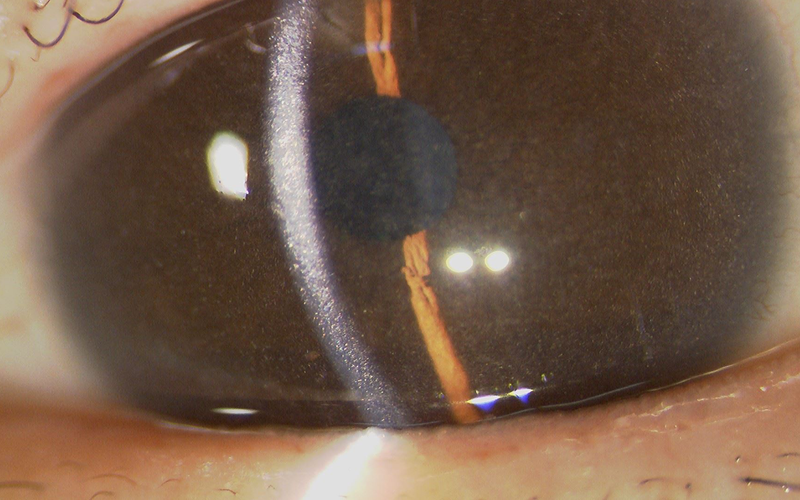

シスチン症は、ライソゾーム膜に存在するシスチン輸送体であるシスチノシン遺伝子の変異により発症する常染色体劣性遺伝形式の先天代謝異常症です。全身にシスチンが過剰蓄積することで様々な臨床症状を呈し、眼球に対しても、角膜、結膜、虹彩、網膜などにシスチン結晶が蓄積することが知られています。この疾患には、シスチン除去薬であるシステアミンの全身投与を行いますが、角膜が無血管組織であることから、角膜シスチン結晶に対しては治療効果が期待できないことが問題でした。

シスチン症は非常に希少な疾患で、眼科医の中でも認知度は低いと思われますが、その診断において「角膜シスチン結晶の同定」が重要な鍵となります。

眼科の先生方には、ぜひスリット画像を頭の片隅に記憶していただき、早期診断につなげていただきたいと考えます。